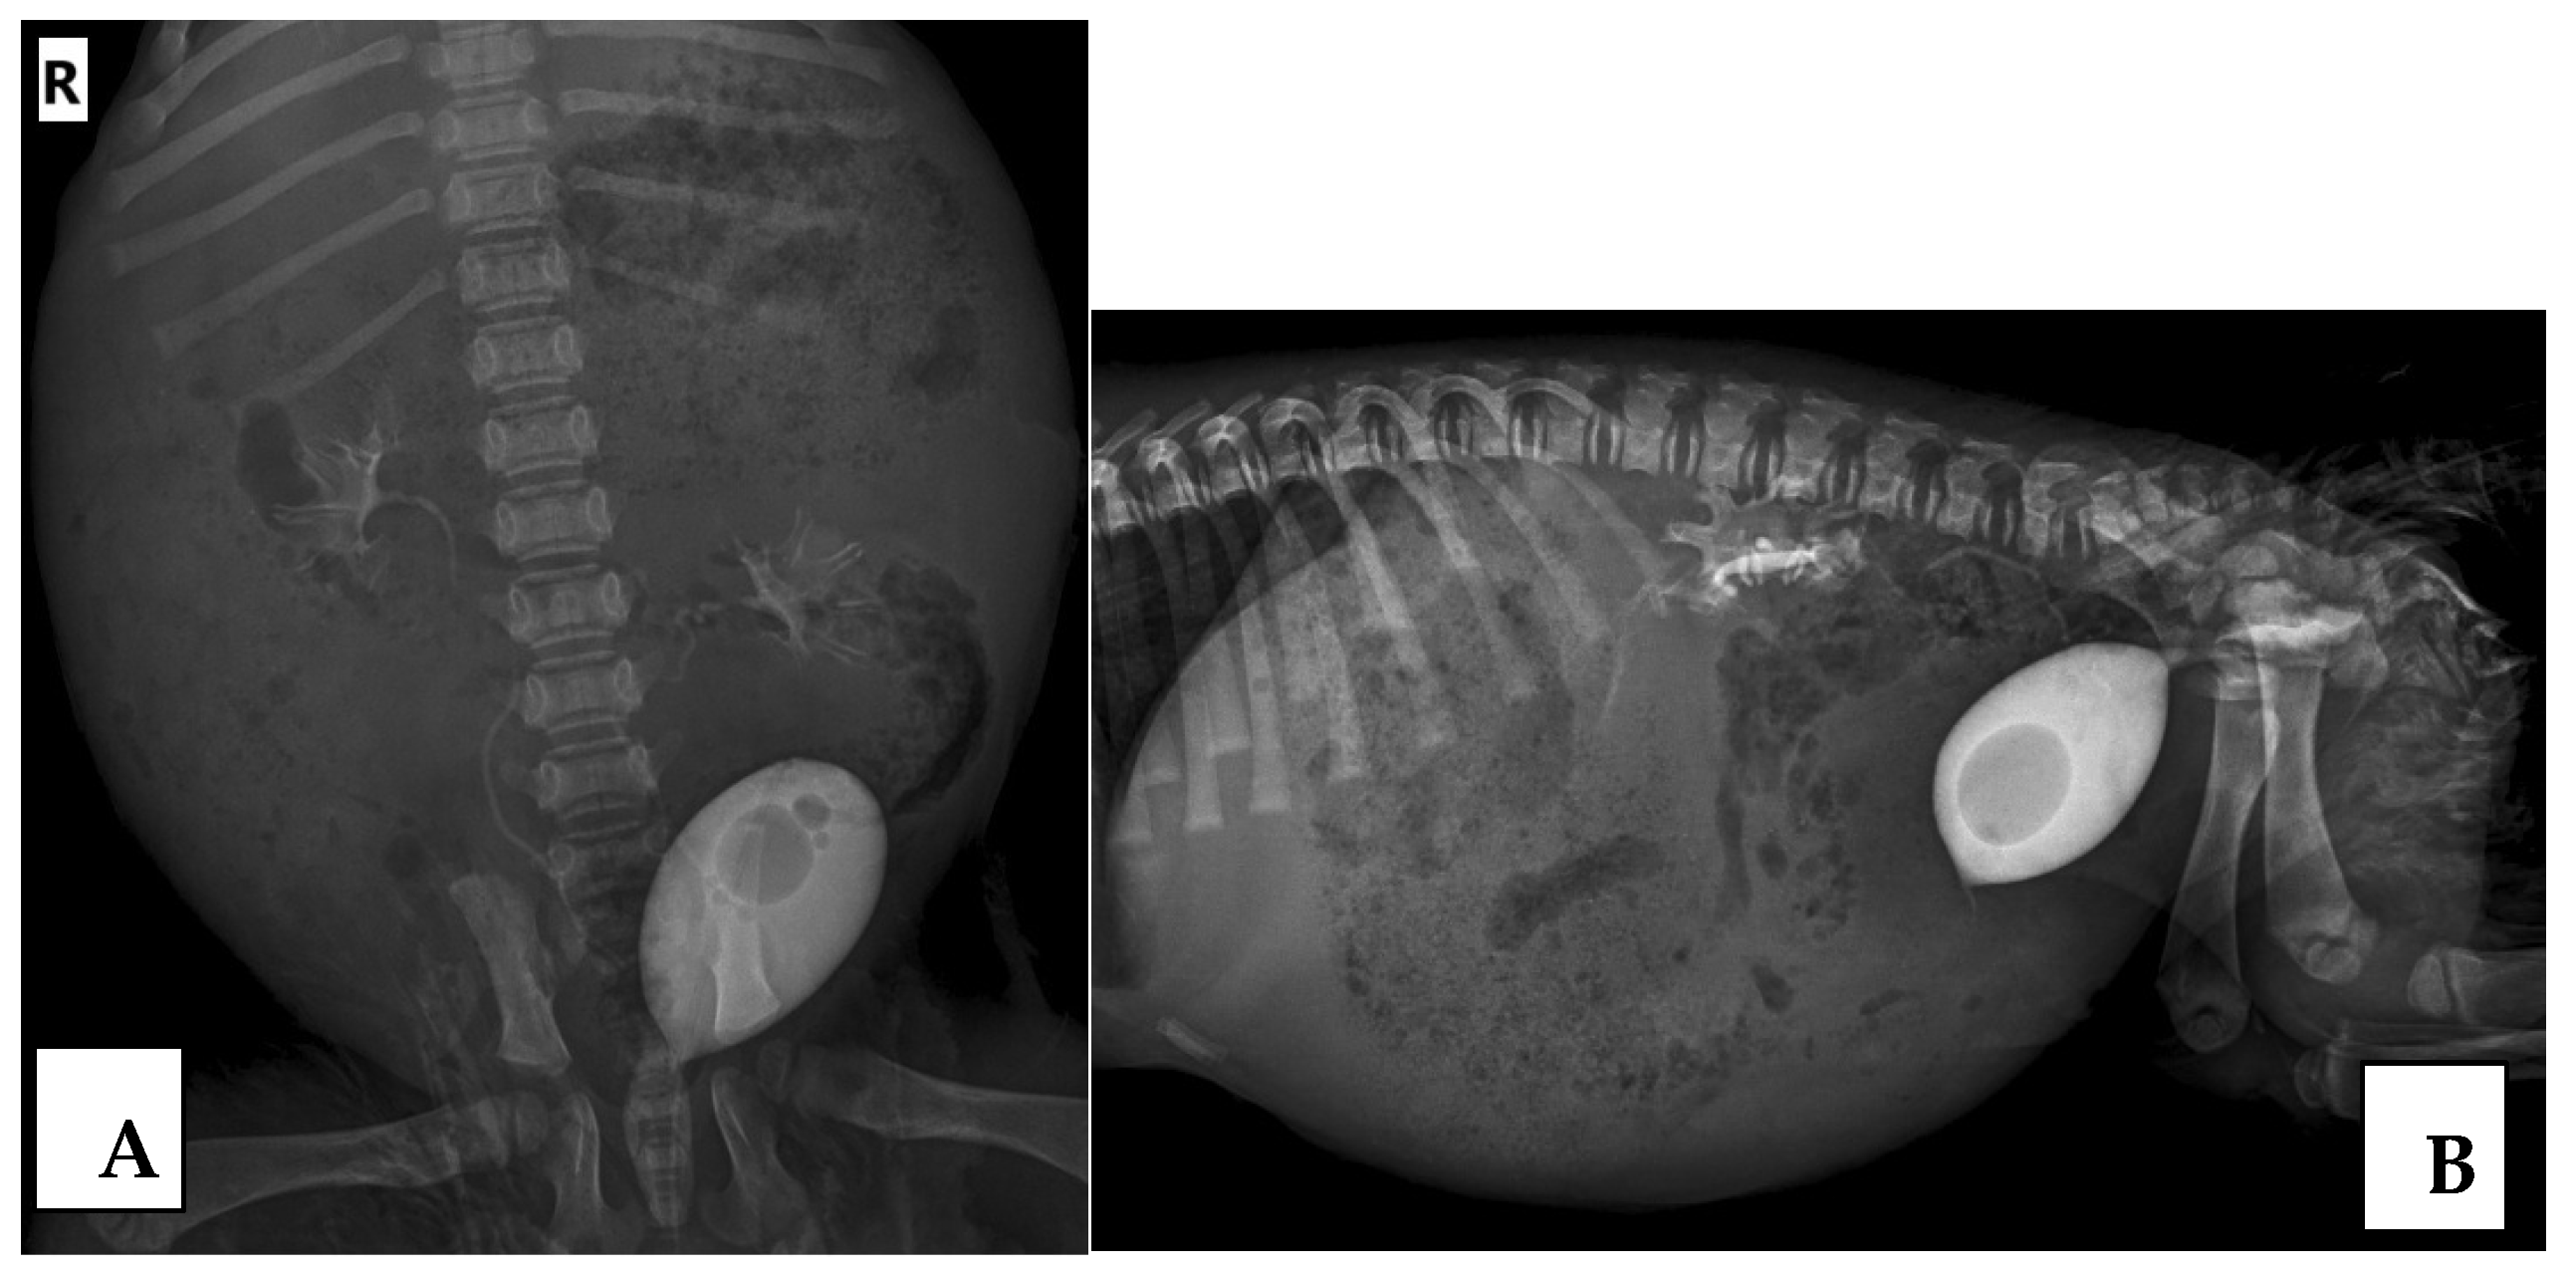

The results regarding the presence or absence of VUR by RCUG (Figure 1) and CE-VUS (Figure 2) were consistent in 117/124 UUs (94.4%). VUR on either method was found in 23/124 UUs (18.6%). VUR was detected with both imaging methods in 16/124 UUs (12.9%), by only CE-VUS in 6/124 UUs (4.8%), and by only RCUG in 1/124 UUs (0.8%). No reflux was detected in 101/124 UUs (81.4%) by both methods.

Figure 1.

Vesicoureteral reflux (VUR) grade II in both the left and right kidney demonstrated on the retrograde cystourethrography (RCUG). The ventrodorsal (A) and lateral (B) view of the RCUG in the same dog.